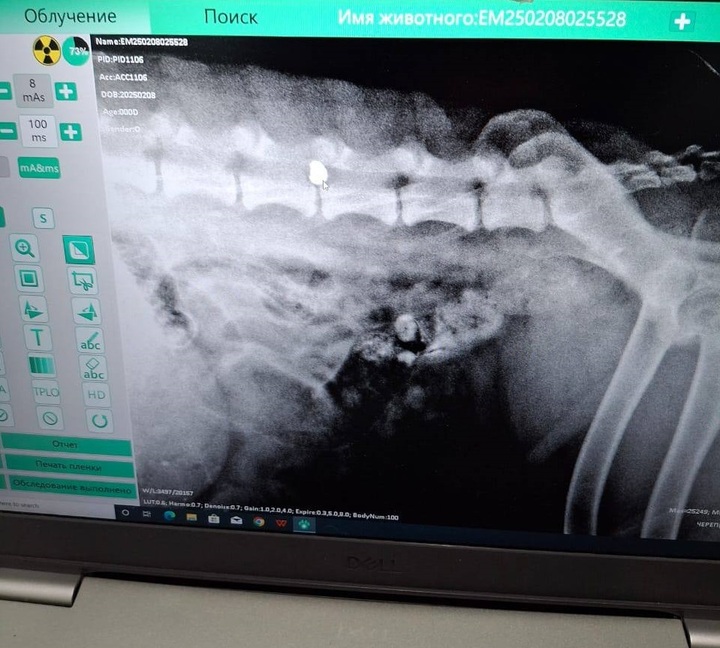

Раненую собаку отвезли в ветклинику. После осмотра специалисты заключили – в позвоночнике застряла пуля от «пневматики». Среди волгоградцев уже нашлись неравнодушные люди, которые были готовы забрать пса.